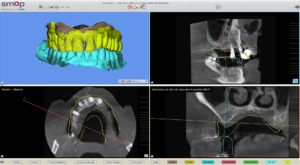

La planification implantaire a été réalisée sur le logiciel SMOP. Les empreintes ont été superposées avec le cone beam du patient.

Les implants ont été posés virtuellement, ce qui a permis au praticien d’évaluer la possibilité d’extraire, implanter et mettre en charge immédiatement lors d’une même séance.

Une fois la planification validée, un guide implantaire SMOP a été dessiné et imprimé (imprimante STRATASYS poly-jet avec précision à 16 microns ).

Le praticien a choisi de poser 2 implants Thommen en FULL GUIDED.